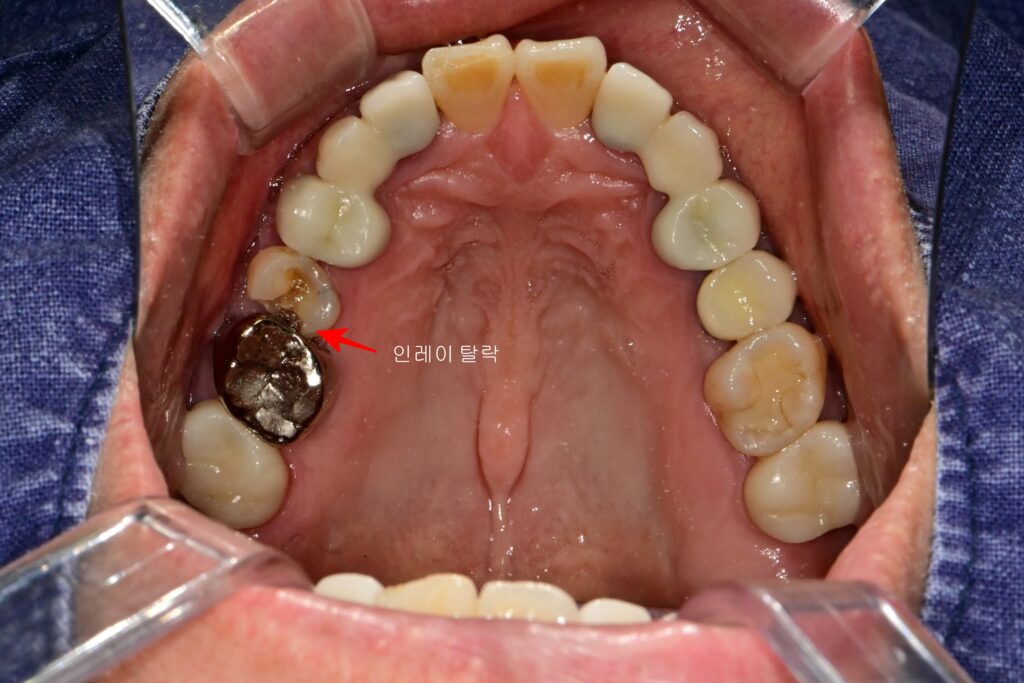

1-1. 인레이 탈락과 깊은 이차우식의 발견

오른쪽 위 어금니에 예전에 치료받았던 인레이가 탈락하여 내원하신 환자분의 케이스입니다.

- 상태 진단: 인레이 하방으로 꽤 깊은 이차우식이 진행되고 있었습니다.

- 추가 문제: 반대편 인접면에도 충치가 발견되었습니다.